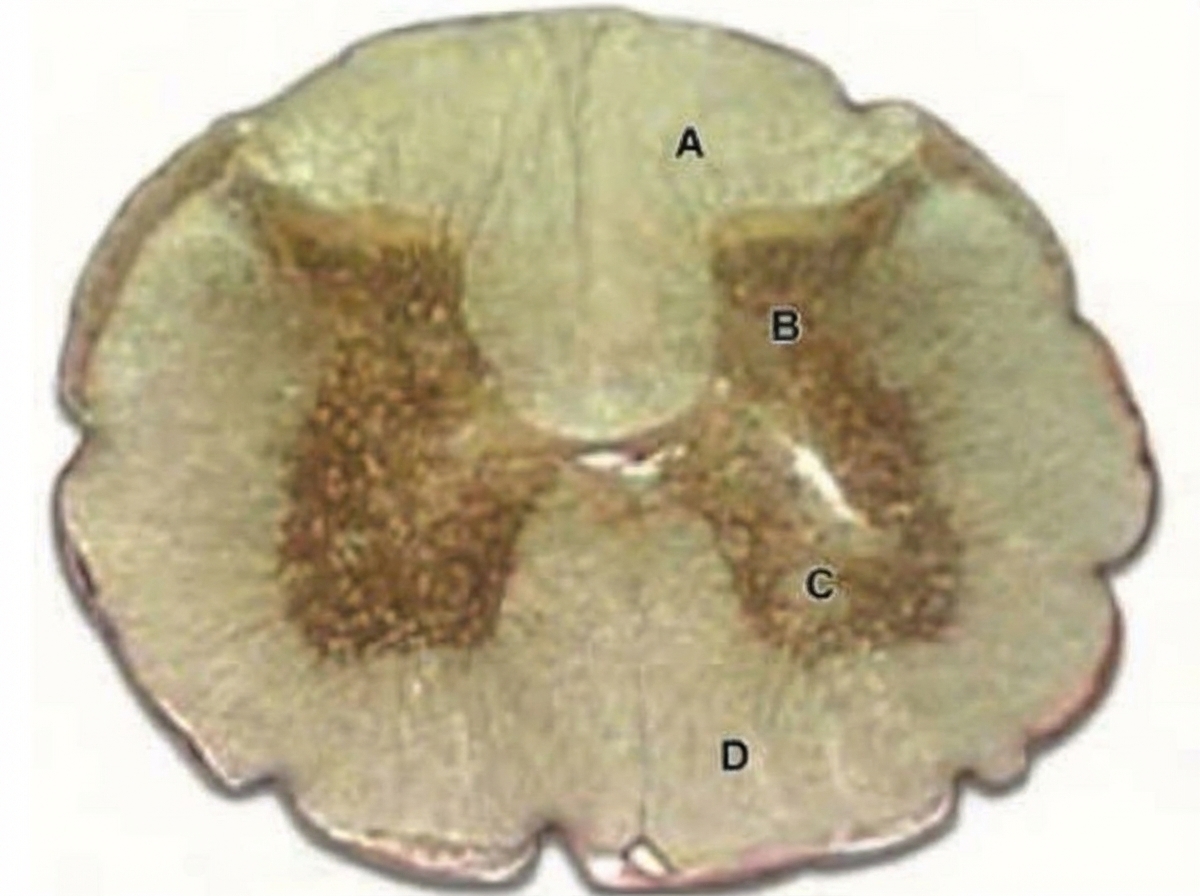

Question 65: In the given slide of cerebellum, the marked cell is inhibitory to?

Explanation: ***Deep nuclei of cerebellum*** - The image shows a **Purkinje cell** (large, flask-shaped neuron with a prominent nucleolus, indicated by the arrow) located in the cerebellum. - Purkinje cells are the sole output neurons of the cerebellar cortex and exert an **inhibitory (GABAergic)** effect primarily on the **deep cerebellar nuclei.** *Vestibular nuclei* - While Purkinje cells of the **flocculonodular lobe and vermis** project to the vestibular nuclei, the primary and most direct inhibitory target discussed in the general context of Purkinje cell output are the deep cerebellar nuclei. - The Vestibular nuclei receive input from the cerebellum, but are not the sole or primary direct targets of all Purkinje cells. *Anterior horn of spinal cord* - The anterior horn of the spinal cord contains **motor neurons** and interneurons involved in motor control, but it does not receive direct innervation from Purkinje cells. - Cerebellar output influences spinal cord activity indirectly via relays in the brainstem and other motor control centers. *Basal ganglia* - The basal ganglia are subcortical nuclei involved in motor control and learning, forming a distinct neural circuit separate from the cerebellum. - There are **no direct inhibitory projections** from cerebellar Purkinje cells to the basal ganglia.